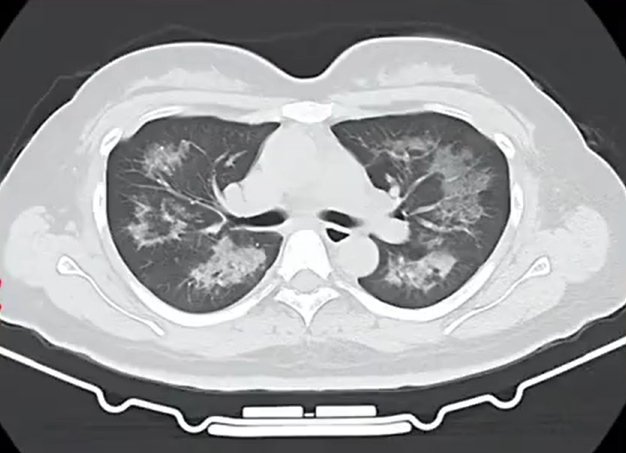

胸部CT进一步显示,她的双肺出现多发斑片状模糊影,被诊断为间质性肺炎。医生判断,病因很可能与她近期长期接触的某类物质相关。经过反复细致地询问病史,小江才说出自己长期、频繁使用定妆喷雾的习惯。